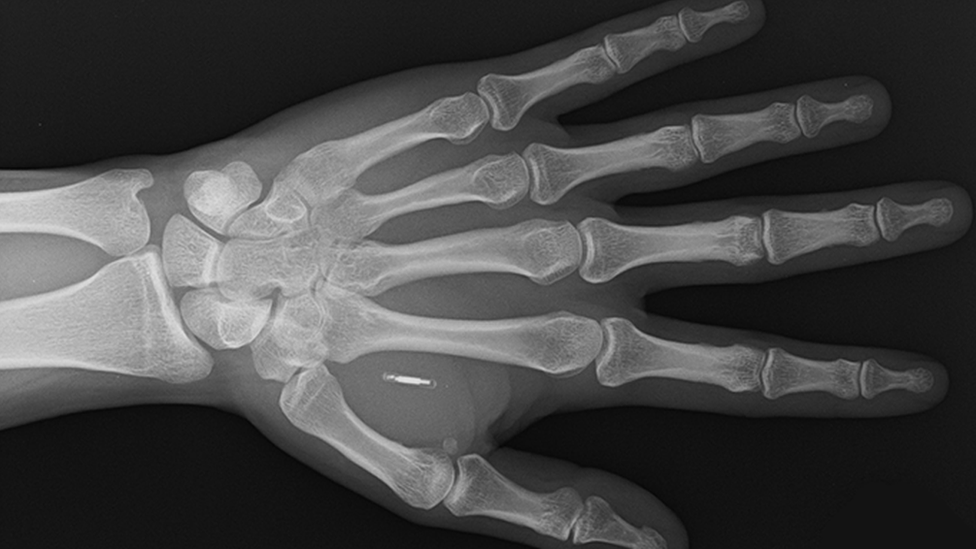

On može da plaća rukom zato što mu je 2019. godine ispod kože ubrizgan beskontaktni mikročip za plaćanje nešto veći od zrnca pirinča.

„Zahvat boli kao kad vam neko uštine kožu", kaže Pauman.

Voletmorov implantat, koji teži manje od grama, sastoji se od sićušnog mikročipa i antene obložene biopolimerom - materijalom prirodnog porekla sličnom plastici.

U Holandiji, Paumanov čip za plaćanje ima ugrađeno LED svetlo sa kinetičkim izvorom napajanja preko kretanja njegovog tela.